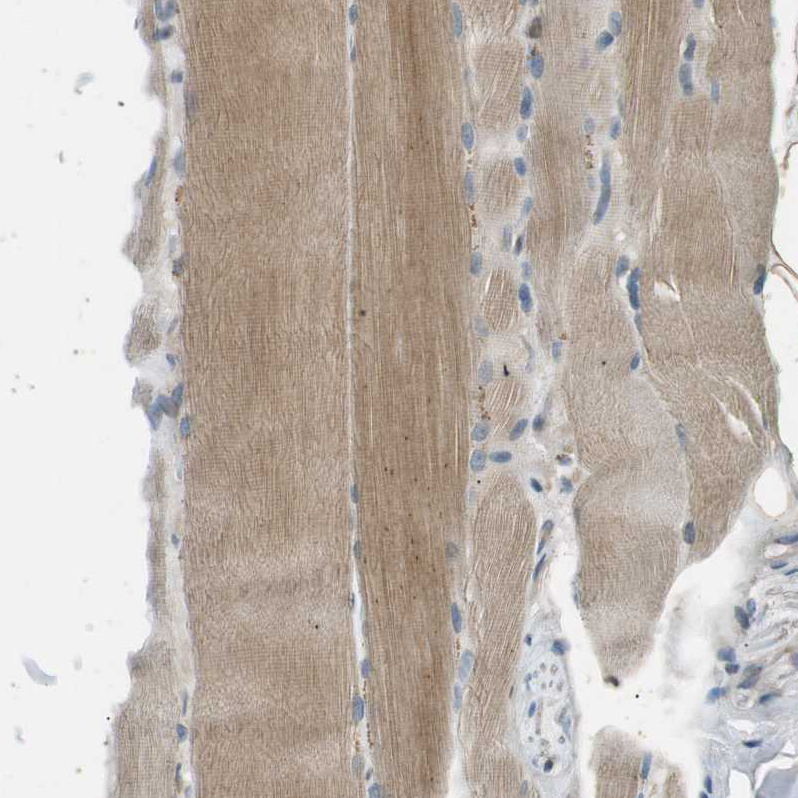

Immunohistochemical staining of human cerebral cortex shows moderate to strong cytoplasmic positivity in neurons.